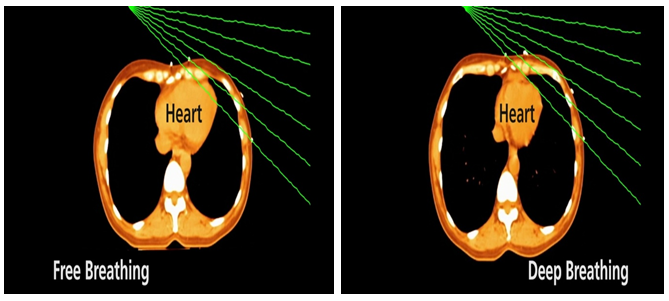

Ở người bệnh ung thư vú, đặc biệt là vú bên trái, tim nằm rất gần vùng cần chiếu xạ. Một số nghiên cứu đã cho thấy nguy cơ biến cố mạch vành nặng có thể tăng 7,4% cho mỗi 1 Gy liều trung bình vào tim, và không ghi nhận ngưỡng an toàn rõ ràng. Vì vậy, kỹ thuật DIBH được phát triển nhằm giải quyết vấn đề này bằng một cơ chế hiệu quả: khi người bệnh hít sâu, phổi giãn nở tối đa, tim được kéo ra xa thành ngực, từ đó tạo thêm khoảng cách an toàn tự nhiên giữa tim và vùng chiếu xạ. Nhờ vậy, tia xạ vẫn tập trung vào thể tích đích trong khi liều vào tim được giảm đáng kể. Trong một số nghiên cứu, DIBH giúp giảm liều tim trung bình từ 6,9 xuống 3,9 Gy; một nghiên cứu khác ghi nhận nguy cơ biến cố mạch vành 10 năm ước tính giảm từ 4,03% xuống 2,55% khi áp dụng DIBH thay cho thở tự do.

Nói cách khác, DIBH không làm thay đổi mục tiêu điều trị ung thư, nhưng làm thay đổi cách chúng ta tiếp cận điều trị: vẫn nhắm chính xác vào thể tích đích, nhưng chủ động tạo thêm khoảng cách an toàn để bảo vệ tim tốt hơn. Đây chính là giá trị cốt lõi của kỹ thuật này.